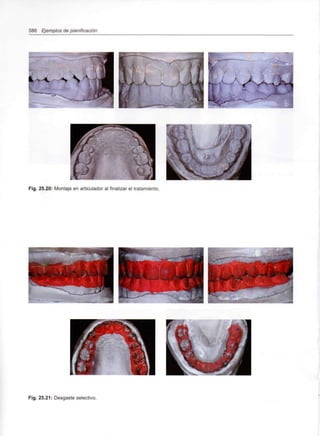

Capítulo 25 - Casos clínicos

553

555

557

571

575